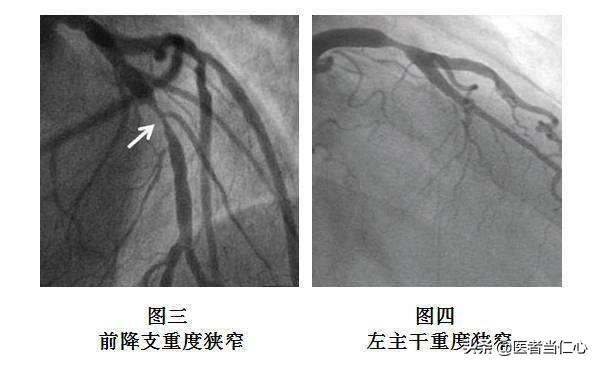

Pour ceux qui ne peuvent être diagnostiqués ou confirmés à 100 %, un scanner coronaire peut être réalisé. Le scanner coronaire permet de voir si les vaisseaux sanguins sont rétrécis et dans quelle mesure ils sont rétrécis, et de confirmer le diagnostic de maladie coronarienne. Pour les patients atteints d'une maladie coronarienne typique, une coronarographie complémentaire peut être effectuée pour confirmer le diagnostic d'une part, et pour poursuivre le traitement d'autre part.

①Diagnostic clair.Le diagnostic de la maladie coronarienne n'est pas difficile à établir avec le niveau actuel des soins médicaux.coronarographieUn diagnostic définitif de la maladie coronarienne peut être posé. Un cathéter est introduit dans les artères directement jusqu'aux artères coronaires, puis un produit de contraste est libéré pour visualiser les artères coronaires, ce qui donne une image claire de l'emplacement et de l'étendue de l'obstruction, et fournit une base pour le traitement ultérieur. C'est pourquoi il s'agit également du traitement le plus courant de la maladie coronarienne.L'"étalon-or" pour le diagnostic de la maladie coronarienne.。

Bien que les symptômes d'angine de poitrine, l'élévation du taux de troponine et les modifications de l'électrocardiogramme soient utiles au dépistage de la maladie coronarienne, l'étalon-or du diagnostic de la maladie coronarienne est la coronarographie, qui est une procédure invasive mais qui joue un rôle irremplaçable dans le diagnostic de la maladie coronarienne et dans la compréhension de la sévérité de la maladie. Grâce à l'injection d'un produit de contraste, la coronarographie permet d'observer clairement le degré de rétrécissement de l'artère coronaire, et lorsque le rétrécissement de l'artère coronaire atteint 50 %, la maladie coronarienne peut être diagnostiquée. La coronarographie permet également de comprendre les parties malades et la quantité de l'artère coronaire, ce qui peut fournir des indices très précieux pour l'évaluation de l'état de la maladie. Certains d'entre vous se demandent peut-être si la maladie coronarienne peut être guérie. Avec la technologie médicale actuelle, nous ne pouvons pas guérir la maladie coronarienne. Toutefois, le risque de progression vers l'infarctus du myocarde peut être réduit par un traitement rationnel, comprenant l'application de médicaments antiagrégants plaquettaires tels que l'aspirine ou le clopidogrel, l'utilisation de médicaments stabilisant la plaque tels que les statines, etc., ainsi que des médicaments améliorant le pronostic tels que les bêtabloquants et le priligy, etc. la maladie coronarienne.